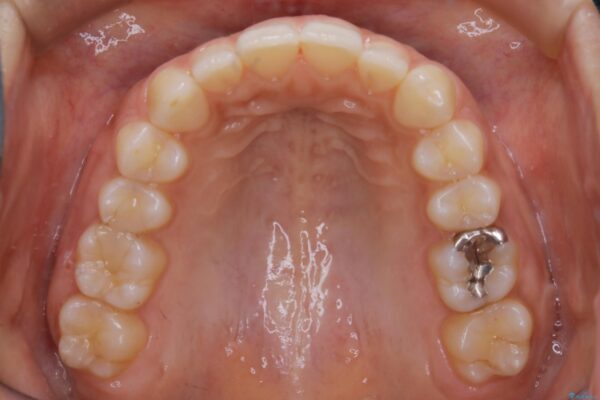

気になるガタツキと噛み合わせを改善したいとご来院されました。

下の歯列よりも上の歯列が前に出ている状態を治すため、マウスピース矯正に加え、患者様にゴムかけのご協力をいただきました。その結果、ガタつきが改善し、上下の噛み合わせが適切な位置で合うようになりました。

歯並びが悪くなる原因の一つに「歯列弓の狭窄」というものがあります。

奥歯や前歯が内側(舌側)に倒れ込んでしまったり、歯が生えてくる位置が内側になってしまうことにより歯並びのアーチが狭くなってしまうことを言います。

このような場合、歯並びのアーチを拡大してあげるだけでもガタつきを無くすためのスペースがかなり作れることがあります。